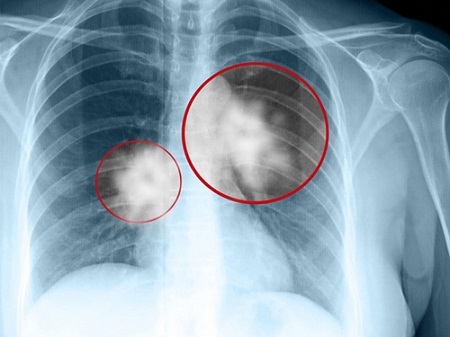

Ung thư phổi đang là loại ung thư gây chết nhiều nhất tại Mỹ, cũng như Việt Nam. Người hút thuốc có nguy cơ bị ung thư phổi cao gấp 20-30 lần so với người không hút. Người hút thuốc cũng có nguy cơ bị 18 loại ung thư khác cao hơn người không hút, bao gồm các ung thư thanh quản, bàng quang, cổ tử cung, dạ dày và đại tràng.

Tại Việt Nam, theo thống kê của WHO năm 2012, ung thư phổi đứng thứ 2 về số ca tử vong với gần 20.000 người chết (tỷ lệ chuẩn hoá theo độ tuổi là 22,6 người trên mỗi 100.000 dân số), chỉ đứng sau (khoảng 21.000 ca tử vong, tỷ lệ chuẩn hoá theo độ tuổi là 23,7/100.000).